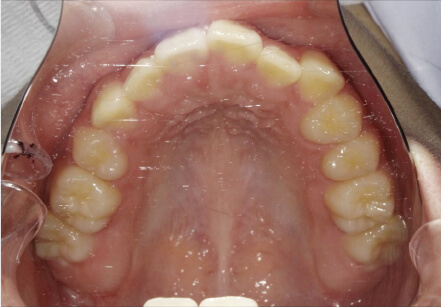

叢生の症例

11歳

女性

歯が重なっている。

カウンセリング・診断結果

臼歯部のOpen改善、インビザライン

治療内容・方法

全額アライナー矯正

術後の経過・現在の様子

クリアライナー使用

費用・治療期間

マイオ 275,000円(月々22,000円)+インビザ移行料金220,000円(月々27,500円)、2年6ヶ月+myo1年